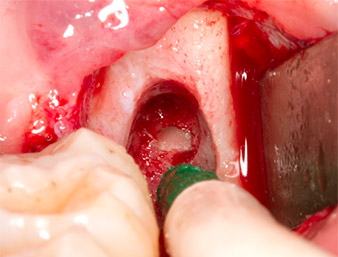

To obtain autogenous material for subsequent wound treatment, healthy bone chips were harvested from the surroundings of the root remnant with a piezo surgical instrument (Piezomed B5) (Fig. 5).

The autogenous tissue was removed with the scraper-shaped section of the working part of the instrument and stored in a physiological saline solution until further use (cf. Fig. 13).